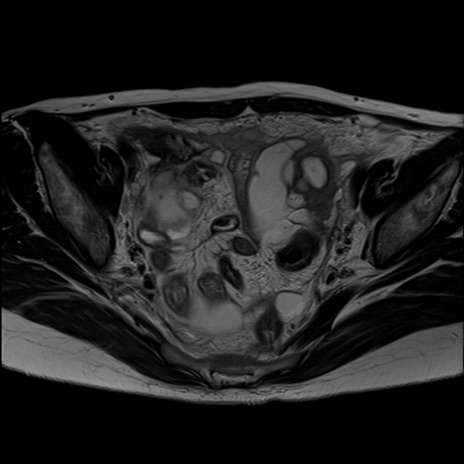

症例39 T2WI(横断像)

【症例】40歳代女性

【主訴】上下腹部痛

【現病歴】2日目から下腹部痛あり。夜間は痛みで眠れなかった。昨日より上腹部痛と下痢が出現。臥位で痛みは軽快したため、休んでいた。本日になって臥位でも立位でも痛みが強くなってきたため救急要請。

【既往歴】子宮内膜症

【身体所見】部:平坦・軟、左上下腹部に圧痛あり、反跳痛あり。

【データ】WBC 21800、CRP 26.78

MRI(4日後)